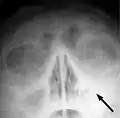

X-ray of left-sided maxillary sinusitis marked by an arrow. There is lack of the air transparency indicating fluid in contrast to the other side.